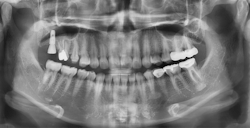

If the bony height defect is not significantly large (residual bone height over 4 mm), a crestal approach is usually adopted. This involves accessing the sinus cavity directly through the dental implant site, typically during implant placement. The traditional osteotome technique, originally proposed in 1994 by Summers,1 involves manually tapping with a mallet specialized instruments into the bone to upfracture the sinus bone and forcibly create space (figures 1 and 2).

As the landscape of implantology evolves, the adoption of hydraulic lifts is poised to become the gold standard in noninvasive sinus lift surgeries, reshaping the future of dental implant procedures (figures 4–11).